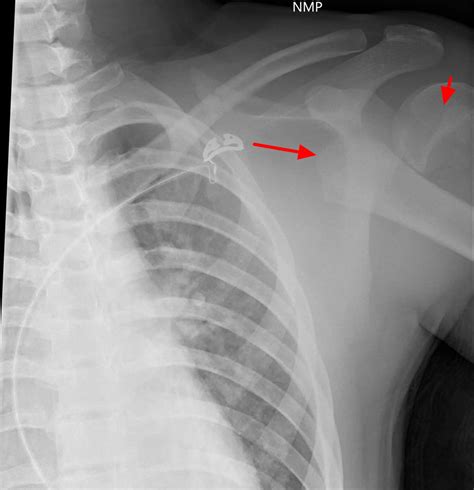

• X-ray Imaging: The primary tool for diagnosis, though it is important to note that growth plates can be difficult to see on standard X-rays, often requiring comparisons to the uninjured limb.

• growth plate fracture xray